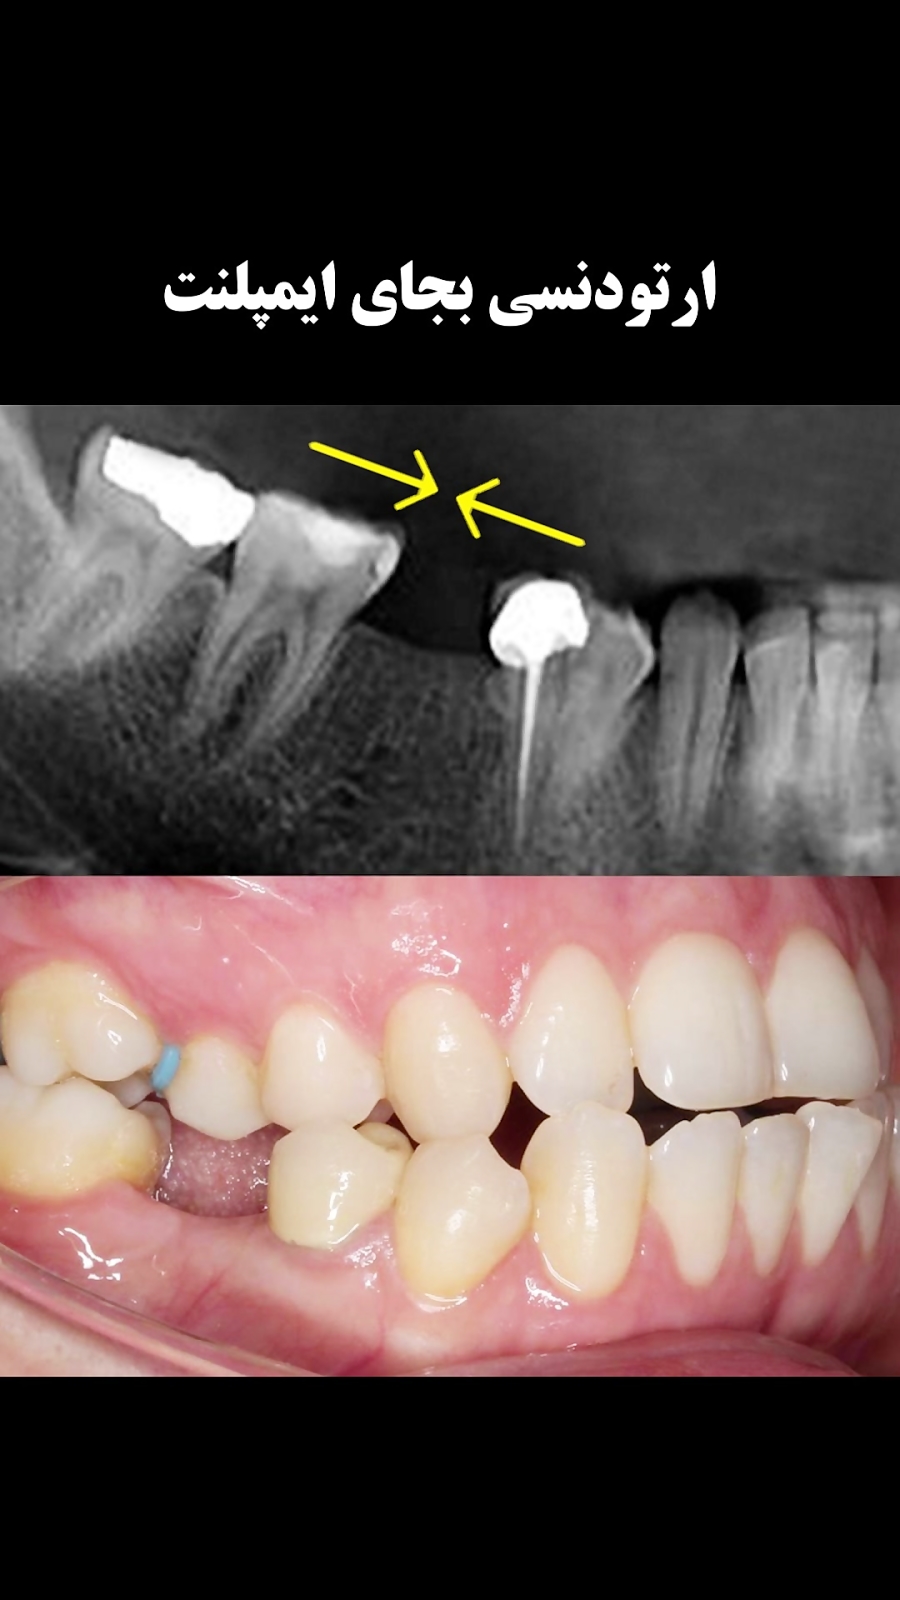

ارتودنسی بجای ایمپلنت| دکتر داودیان

47 بازدید